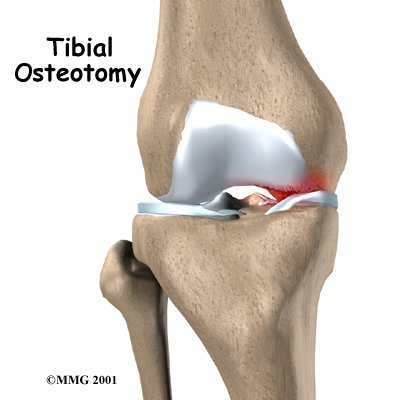

Tibial Osteotomy

Knee osteoarthritis often affects only one side of the knee joint. When this occurs, realigning the angle made between the bones of the leg can shift your body weight so that the healthy side of the knee joint takes more of the stress. The procedure to realign the angles of the lower leg is called a proximal tibial osteotomy.